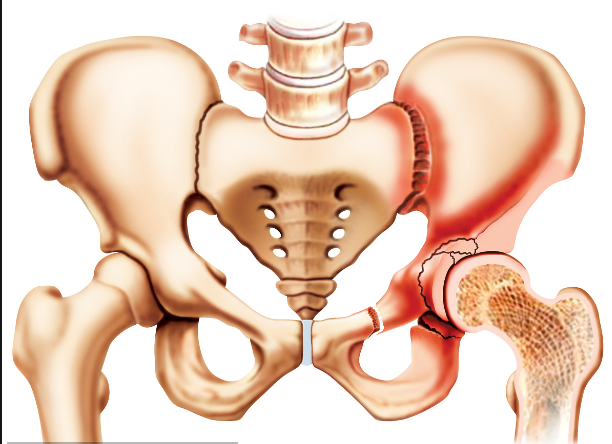

人体的髋关节是一个杵臼关节,就像我们生活中常见的器物杵臼。“杵”就是我们的股骨头,而“臼”就是指我们的“髋臼”。我们知道,正常情况下,“杵”是嵌在“臼”里面的,有丰富的肌肉保护着,但是,当“臼”的结构不正常时,“杵”在肌肉的作用下就会从“臼”里慢慢跑出来,导致无法正常发挥作用。近日,泸州市中医院骨三科开展的市属医院首例髋臼周围截骨术PAO, 就成功为一名成年患者解决了“杵”与“臼”结构不正常的问题。

“髋臼发育不良其根源在婴幼儿时期已经存在,由于未及时发现或治疗不彻底而残留下来 。”泸州市中医院骨三科主任、主任中医师李彬介绍,肖女士的髋臼因发育不良,浅且覆盖少,因此,造成她的髋臼对位不好。在走路时,因为力学原因,髋关节发生摩擦因而产生强烈的疼痛,如果没有得到及时的根治性治疗,她的病情将慢慢发展为软骨炎,最终发生骨性关节炎,影响关节功能活动,最后不得进行髋关节置换。